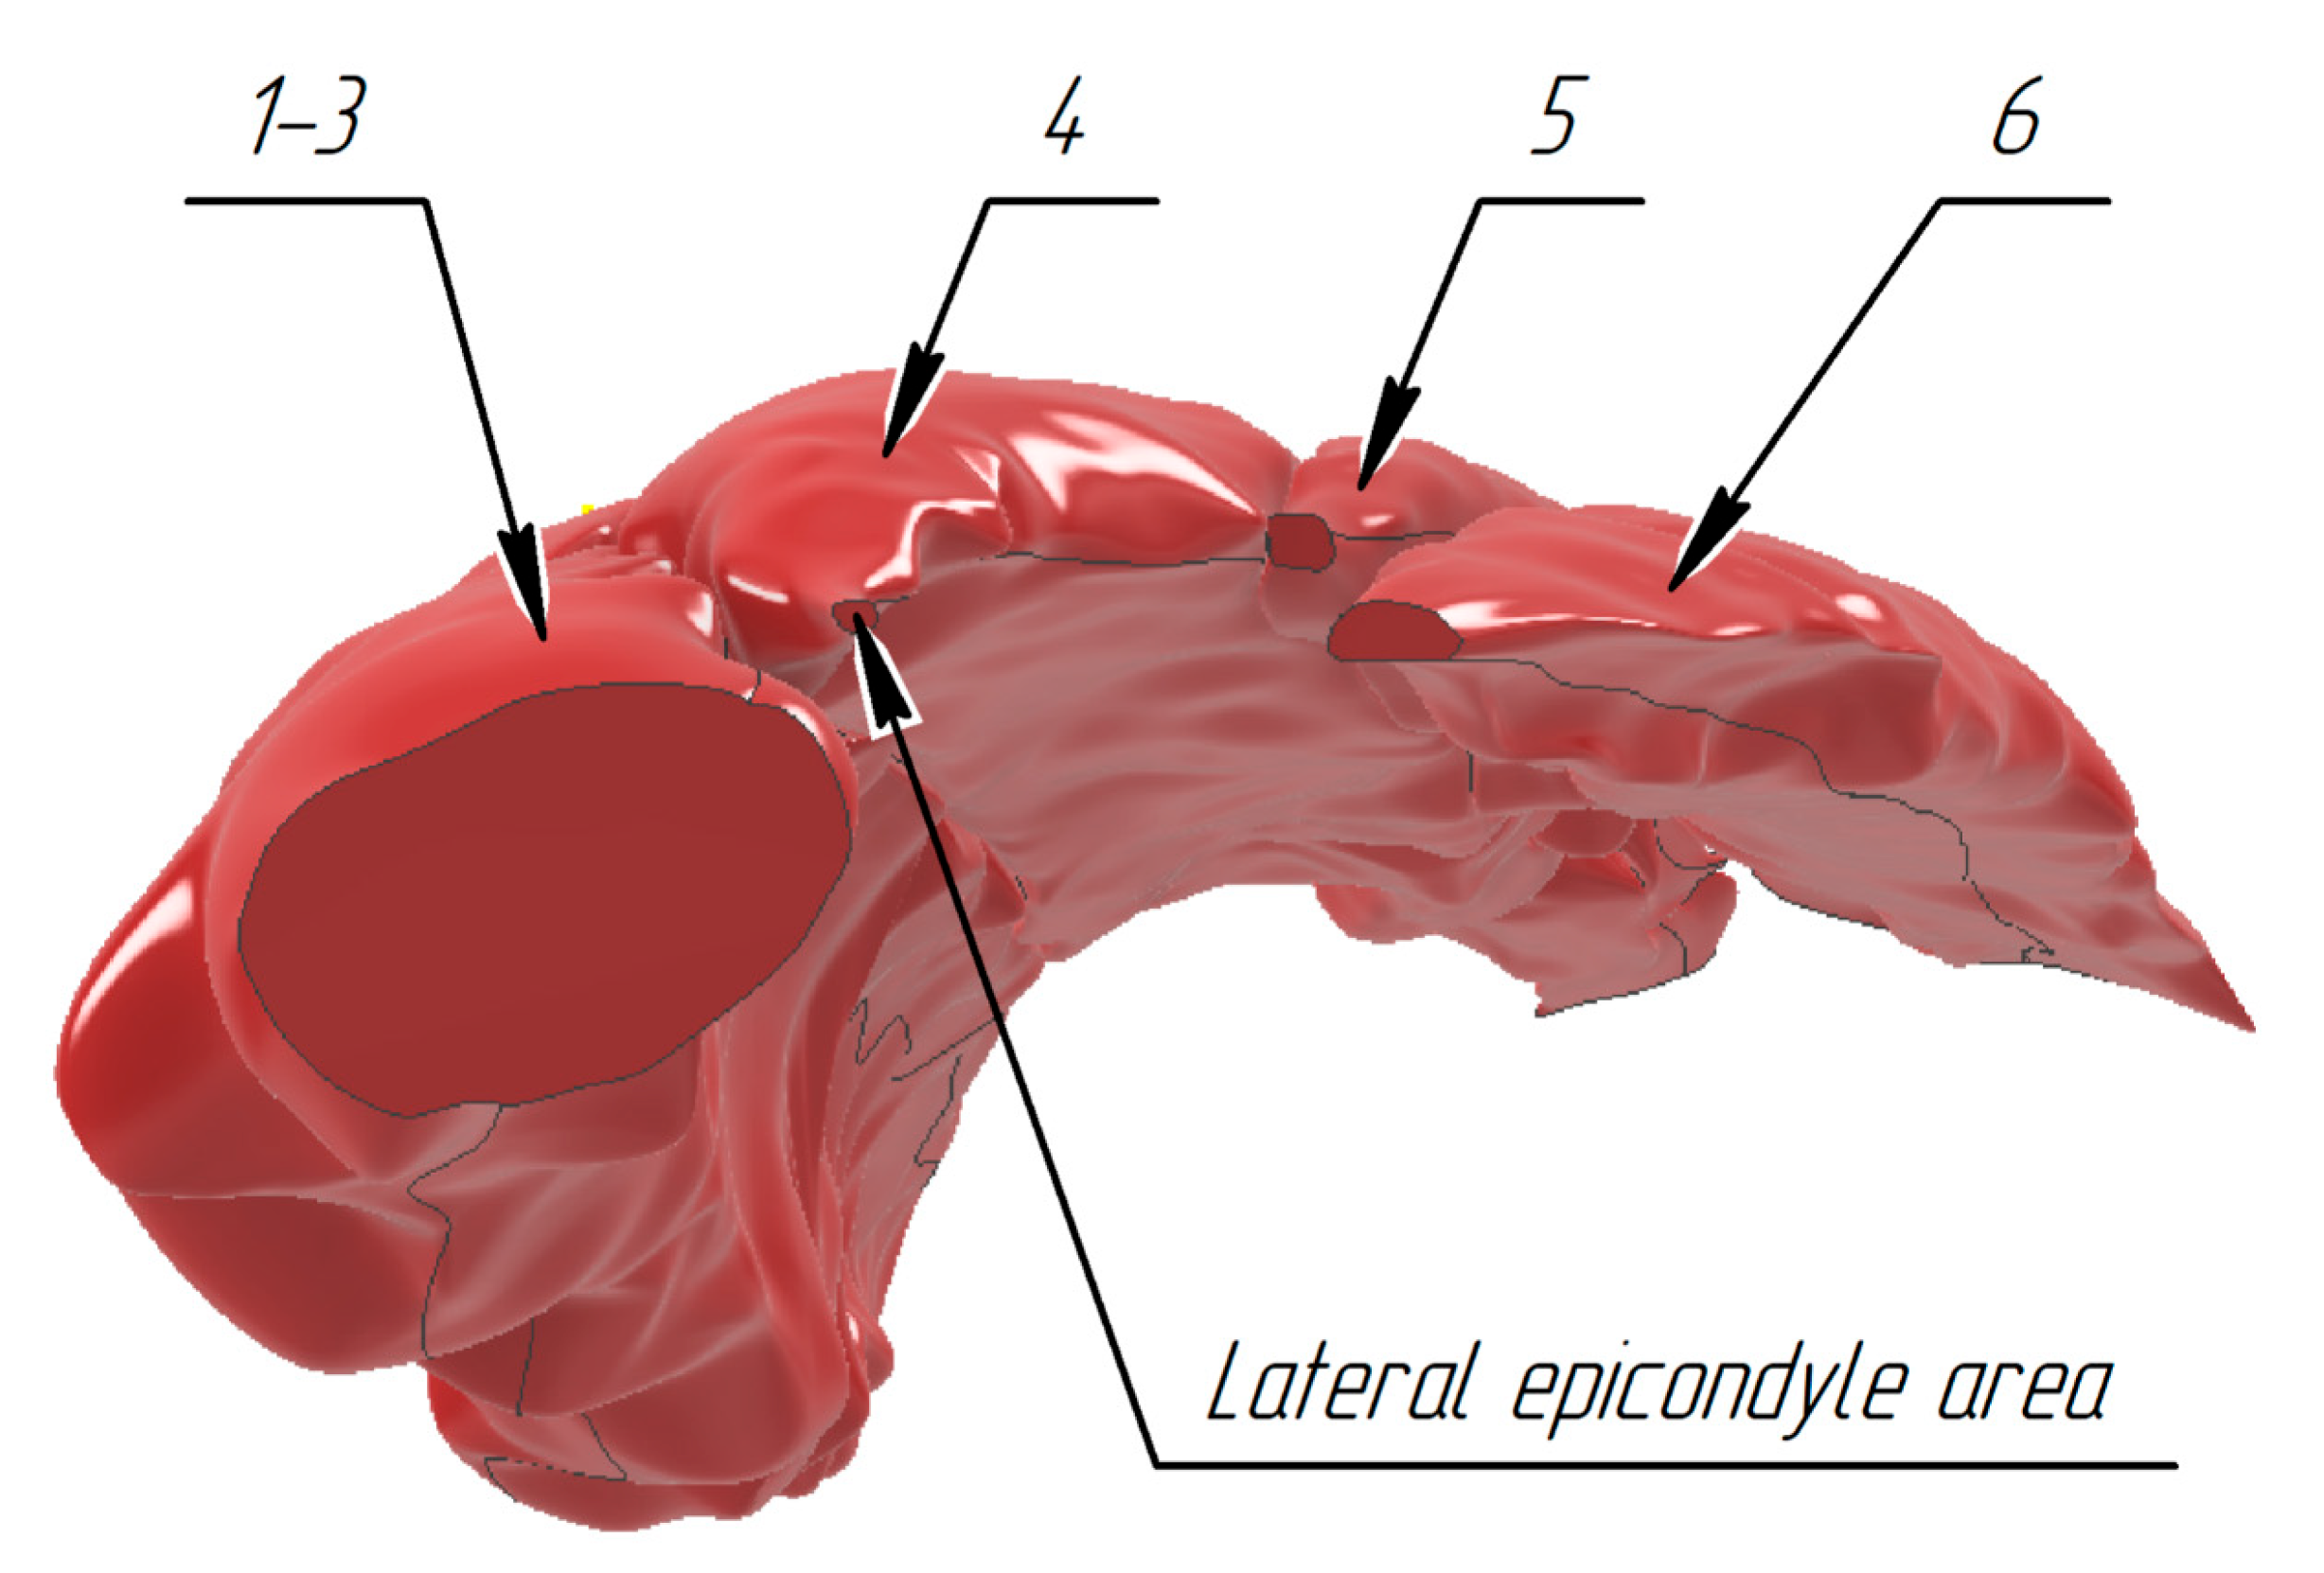

3.1. Construction of the Forearm Muscles’ Volumetric Models